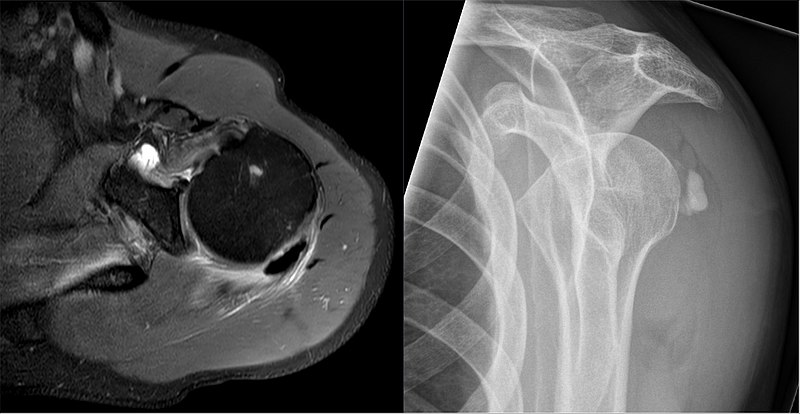

대부분의 석회성 건염의 환자에서, 석회가 형성된 이후 모든 시기에서 단순 X-ray 촬영만으로도 석회의 존재를 확인할 수 있게 됩니다. 대부분의 경우에는 회전근개가 상완골에 붙는 부착부위로부터 1-2cm 상방 부위에 석회 결정이 있는 것을 확인 할 수 있습니다. X-ray 영상상 석회가 명확하게 보일수록 더 질병이 진행되고 통증이 심할 것이라 생각하실 수 있습니다만, 실질적으로는 석회가 솜털같이 보이는 시기가 위에 말씀드린 연고와 같은 형태의 석회 물질을 이루는 용해기여서, 통증이 한층 더 심하다고 할 수 있습니다. 반면에 분필처럼 딱딱하게 경계가 명확하게 나타나는 석회가 발견되는 경우에 환자분들은 오히려 통증을 덜 호소하는 경우가 많습니다.

석회 침착물의 크기가 작거나 용해기처럼 솜털과같은 양상을 띄고 있는 경우에는, 단순 X-ray 촬영보다 초음파 영상을 통해서 진단하는 것이 더 쉽고 정확하게 진단할 수 있습니다. 또한 초음파의 경우 진단적 목적과 함께 병변을 실시간으로 보면서 병변 부위에 동시에 주사치료를 시행할 수 있어 각광받고 있습니다.

이 밖에 환자분들이 정밀검사를 원하셔서 요청하시는 CT나 MRI가 있을 수 있습니다만, CT 촬영은 석회 침착의 위치를 찾는데 3D적인 그림을 제공해준다는 점에서는 의미가 있지만, 치료 방침에 영향을 미칠 정도는 아니기에 일상적으로 추천되진 않습니다. MRI의 경우에는 앞서 언급한대로 석회 침착물이 용해되면서 발생하는 회전근개의 파열 정도를 파악하고, 수술적 처치가 필요할 정도로 손상된 부분이 있는지 확인하는 데에는 유용한 검사입니다.